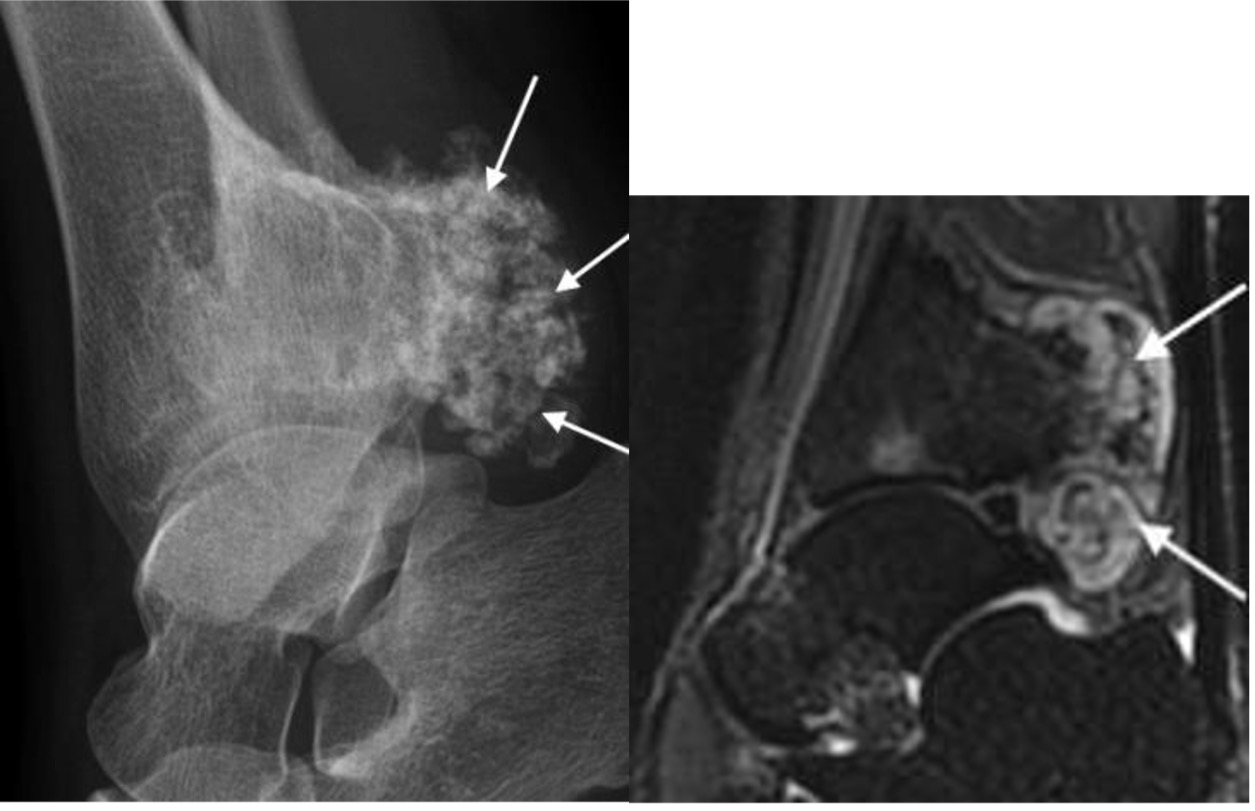

Figure 3. Chondrosarcoma

Chondrosarcoma

- age: 40s – 50s

- most common malignant primary bone tumour

- hindfoot > forefoot

- irregular osseous lesion on plain radiographs

- if intermediate or high-grade, consider amputation